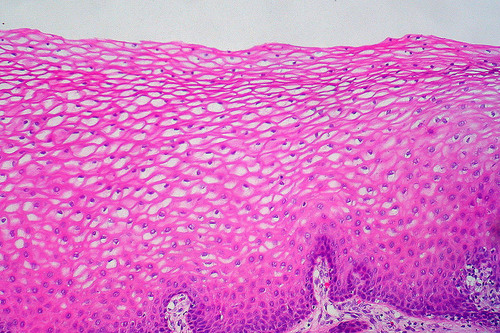

stratified squamous

consist of several layers; functions in protection